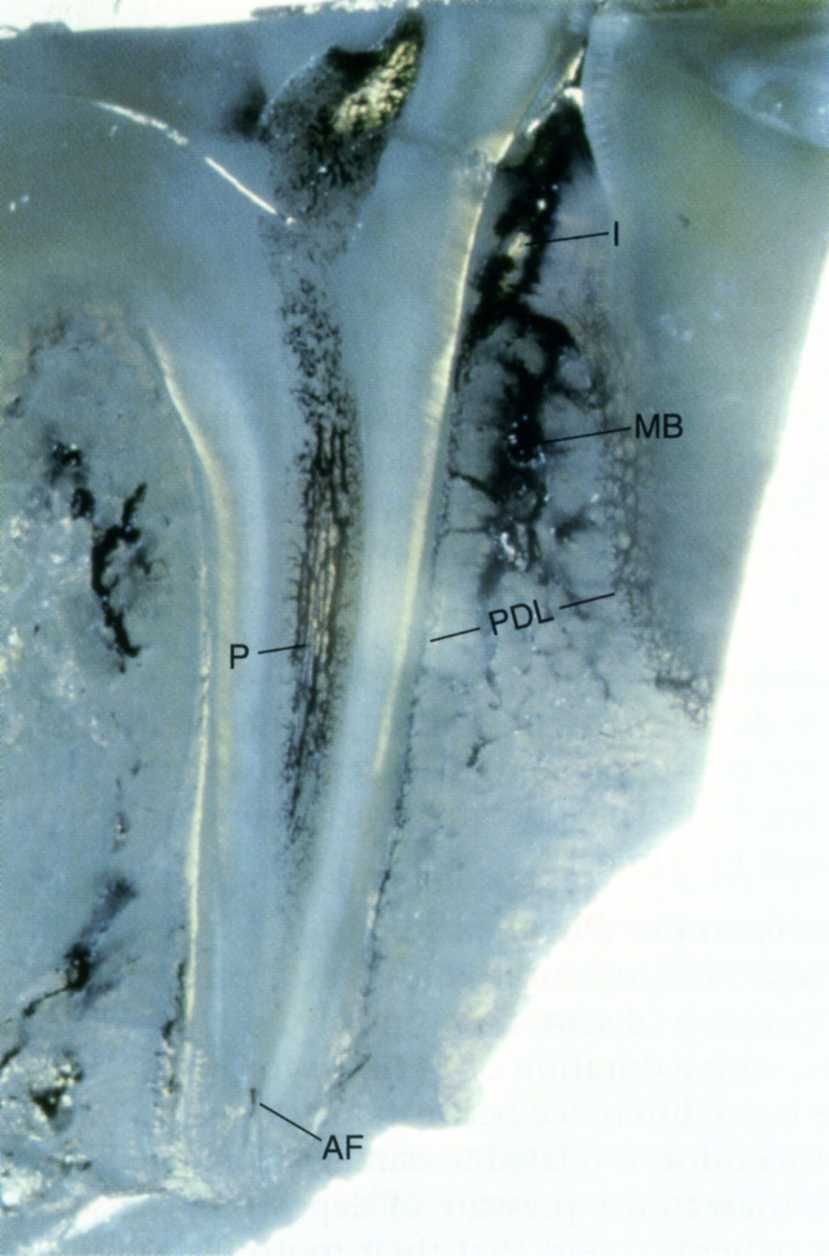

Tuần hoàn và thần kinh vùng chóp chân răng

Giữa răng và xương ổ răng có 1 khe hẹp chứa dây chằng quanh răng, mách máu và thần minh …, Phương pháp gây tê trong điều trị tủy răng này sẽ đưa 1 lượng thuốc tê vào vùng dây chằng quanh răng, thuốc tê theo những lổ rỗng trên bờ xương ổ răng ,đi vào vùng tủy xương và đi tiếp vào hệ thống mạch máu xung quanh răng rồi ngấm vào tủy răng

Hình ảnh cho thấy có nhiều lỗ nhỏ vùng cổ răng trên xương ổ, thuốc tê có thể ngấm qua đây để vào vùng xương tủy